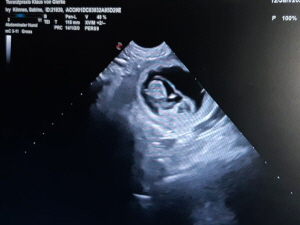

Wir wagen es noch einmal - Anfang 2026 möchten wir mit unsere Ivy einen Wurf haben, unser F-Wurf. Wir freuen uns auf ein Haus voller quirliger, flauschiger, schwarzer Knäuel, die dann bald darauf das Leben einiger Familien bereichern, aber auch die Ambitionen für ‘Arbeit’ im Hundesport oder ähnlichen Bereichen haben und ausgelastet werden müssen.